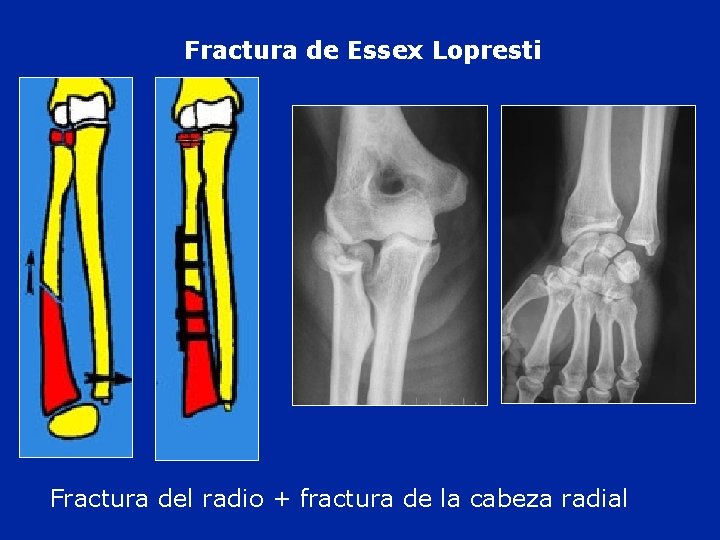

Fractura de Essex Lopresti Fractura del radio + fractura de la cabeza radial